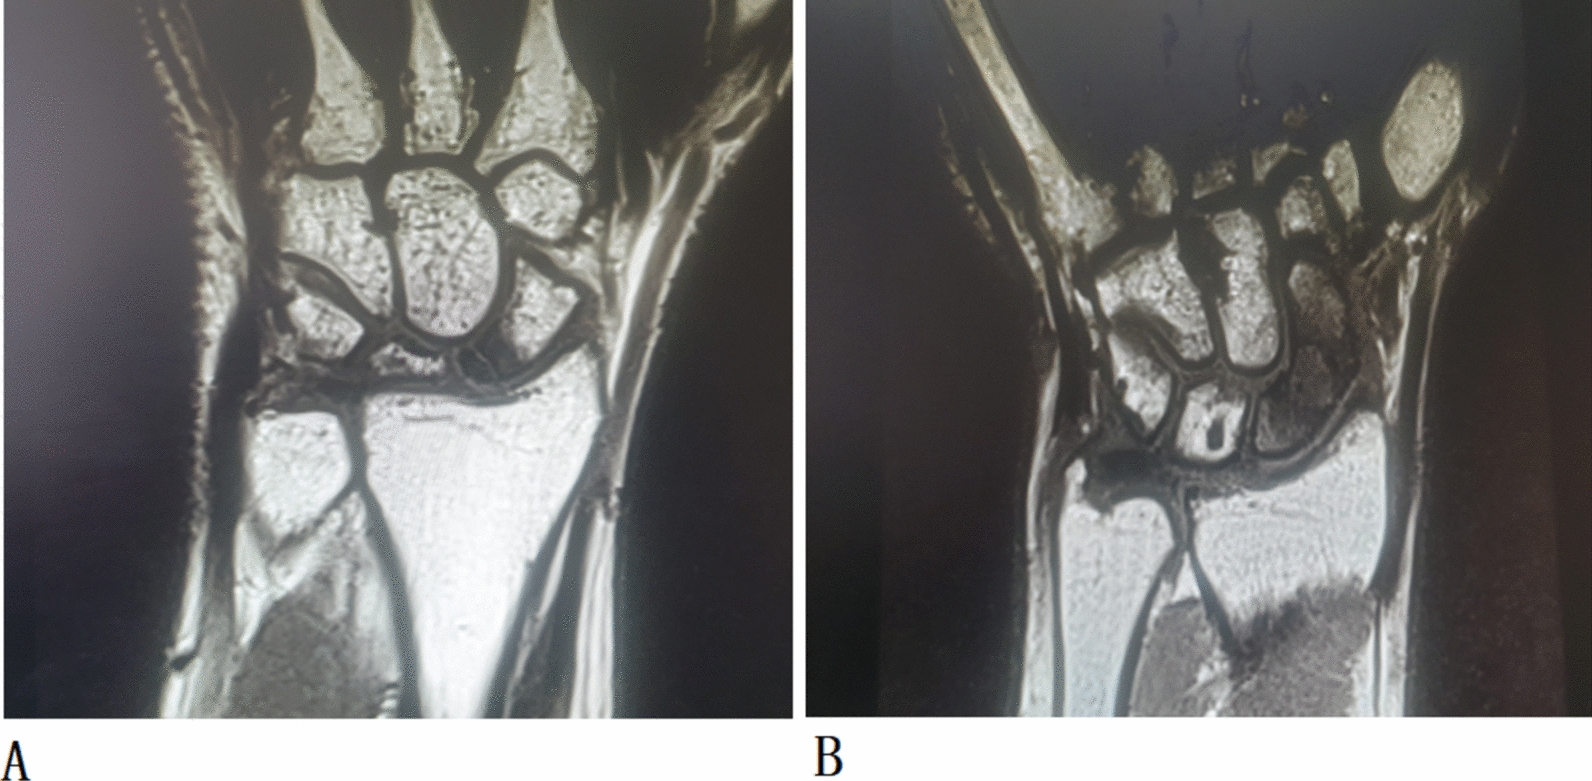

Background: Scaphoid fractures are a prevalent and complex issue in orthopedic practice, particularly when they lead to complications, such as nonunion and avascular necrosis (AVN), especially in proximal pole fractures. Preoperative assessment of scaphoid vascularity using magnetic resonance imaging (MRI) has become increasingly important for guiding surgical interventions, including deciding on using avascular bone grafting or vascular grafting procedures. However, there is ongoing debate regarding the diagnostic accuracy of various MRI techniques in evaluating scaphoid vascularity. This study aims to analyze existing literature on the diagnostic efficacy of different preoperative MRI methods in assessing scaphoid viability in patients with nonunion.

Results: Across three databases yielded 431 articles, of which 14 were selected for meta-analysis. The diagnostic performance of these MRI techniques was evaluated, revealing pooled sensitivity and specificity values of 0.702 and 0.85, respectively. Specifically, unenhanced MRI demonstrated a pooled sensitivity of 0.63 and a specificity of 0.85, while enhanced MRI showed improved sensitivity and specificity at 0.77 and 0.87, respectively, with an area under the curve (AUC) of 0.83 (P < 0.0001).

Conclusions: This meta-analysis indicates that contrast-enhanced preoperative MRI provides superior sensitivity, specificity and AUC to unenhanced MRI for detecting scaphoid vascularity. In addition, the study highlights that the detection of hypointensity is a more reliable predictor of AVN, whereas isointensity may not accurately reflect scaphoid viability. Given the significant heterogeneity among studies and the lack of large, randomized trials, further well-designed studies with adequate sample sizes are necessary to confirm the effectiveness of different MRI methods in preoperatively assessing scaphoid vascularity.